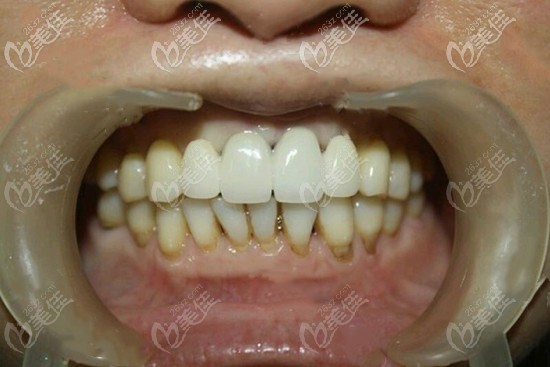

术后照片:

门牙缺失四颗种植案例图片